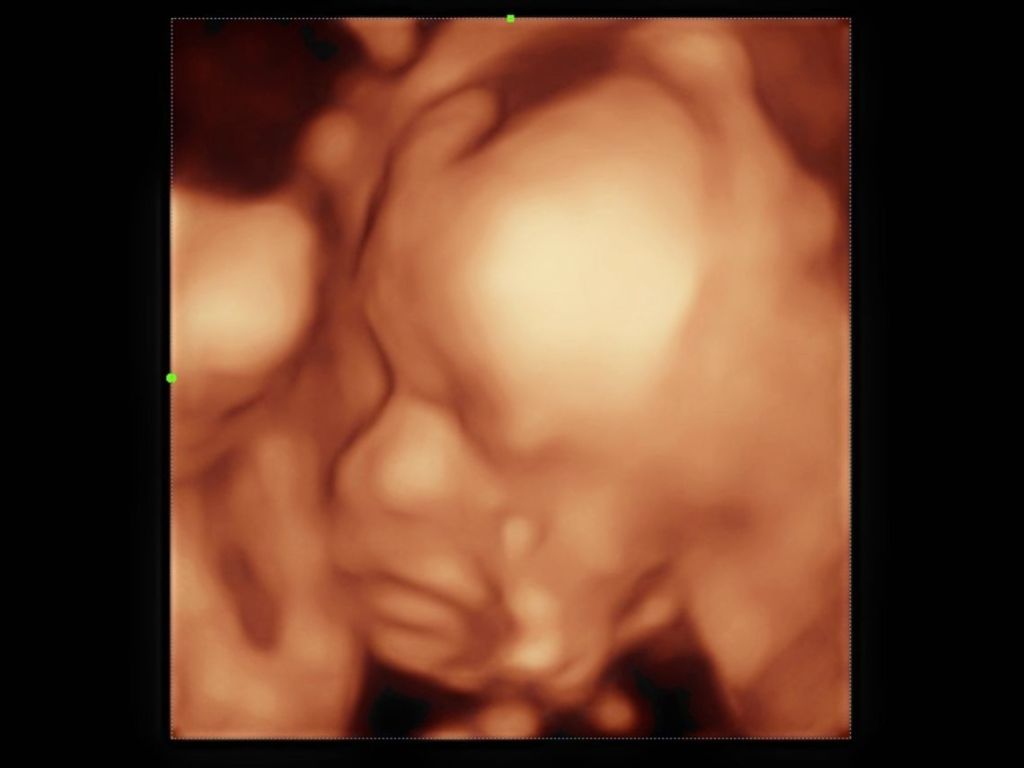

Para determinar si los bebés podían o no distinguir sabores, las autoras de la investigación se basaron en las ecografías 4D, a través de las que observaron cómo reaccionaban a diferentes sabores transferidos al líquido amniótico y su entorno fetal después de haber sido ingeridos por sus madres.

“Los fetos expuestos al sabor de la zanahoria tenían menos arrugas en la nariz, las cejas bajadas, el labio superior elevado, bostezos y giraban más la cabeza que los bebés que no se expusieron a este sabor”, afirma la investigación. Relacionaron todas estas muecas con una “cara de risa”.